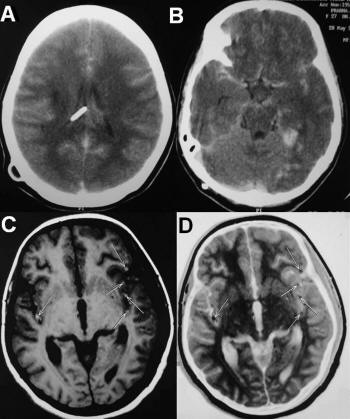

Intracerebral Hemorrhage: An Atypical Presentation

Brain Parenchymal blood collection secondary to local loss of vascular integrity. 3 Pregnancy Trauma Causes : Intracerebral Hemorrhage: an atypical presentation Author: bsharaf Created Date: 5/20/2010 1:57:14 PM ... View Doc

Acute Care Of Patients With Intracerebral Hemorrhage

Acute Care of Patients with Intracerebral Hemorrhage . Declarations • None . Definitions • MRI of brain . Labs • CBC with platelets • BMP • PT/INR • PTT • Serum Glucose • Pregnancy Test • Toxicology Screen • Troponin . General Medical Management . Blood Pressure ... Get Content Here

THE MOTHER OF ALL HEADACHES: INTRACRANIAL HEMORRHAGE IN PREGNANCY

THE MOTHER OF ALL HEADACHES: INTRACRANIAL HEMORRHAGE IN PREGNANCY Amy M. Adelberg, MD Obstetrix Medical Group of Colorado ... Retrieve Here

Germinal Matrix Hemorrhage: Intraventricular Hemorrhage In ...

Germinal Matrix Hemorrhage: Intraventricular Hemorrhage in Very-Low-Birth-Weight Infants Papile.20 The prevalence of GMH-IVH was estimated by brain ultrasound; Multiple pregnancy 30 (35.7) 8 (36.4) 0.955 Prenatal steroids 0.17 ... Document Retrieval

Conservative Management Of Cerebellar Hemorrhage In pregnancy

Conservative management of cerebellar hemorrhage in pregnancy N. Kawasaki, had died of brain apoplexy at age 49, patients with aneurysm and AVM who bleed before the 36th week of pregnancy allows full-term normal delivery. ... Doc Retrieval

Postpartum Angiopathy With Cerebral Infarction, Subarachnoid ...

Postpartum Angiopathy with Cerebral Infarction, Subarachnoid Hemorrhage and Intraparenchymal Hemorrhage: an uncomplicated pregnancy and vaginal delivery. She also reported a remote history initial subarachnoid bleed, the vasoconstriction may be a phenomenon that fluctuates over time. ... Fetch This Document